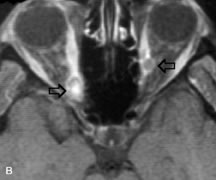

Lymphomas have MRI characteristics similar to those of inflammatory lesions in that they are hypointense to fat and isointense to muscle on T1-weighted images (Fig. 22). They may appear hyperintense to fat on T2-weighted images, perhaps owing to less fibrosis than that seen in orbital inflammatory pseudotumor, although this is not a consistent finding.31,50,66 Lymphoid tumors typically enhance moderately after contrast injection. Unfortunately, studies have shown that tumor density and homogeneity are similar between inflammatory and malignant orbital infiltrates, and MRI cannot differentiate these lesions.72,73

Fig. 22. A and B. T1- and (C) T2-weighted MR scans demonstrate a poorly defined multicompartmental mass enveloping the lateral rectus, superior rectus, and levator palpebrac superioris muscles. The lesion is isointense to brain on T1- and T2-weighted scans, as is typical for highly cellular neoplasms. D. Postcontrast fat-suppressed T1-weighted scan demonstrates intense enhancement of the infiltrating intraconal and extraconal tumor.